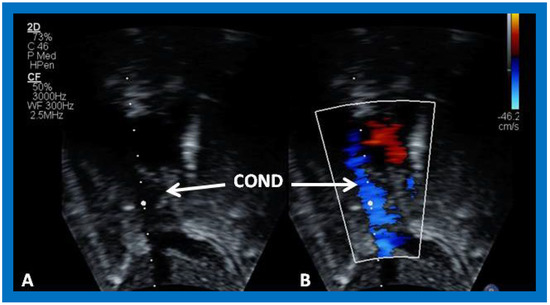

Cross-sectional views of the Fontan conduit were shown in Figure 38, Figure 39 and Figure 40. Imaging of the conduit longitudinally is also possible (Figure 46) and laminar flow in the conduit (Figure 46B) is indicative of a nonobstructive conduit. The connection between the IVC and the conduit (Figure 47 and Figure 48) can also be demonstrated by echo studies. Doppler interrogation demonstrating low flow velocities across this region (Figure 49) is indicative of nonobstructive IVC–conduit junction. Turbulent flow and high Doppler velocity across this region suggest obstruction; however, this is rarely seen.

Figure 39. Selected video frame from an apical four-chamber view demonstrating the left ventricle (LV), hypoplastic right ventricle (HRV) with an atretic tricuspid valve (ATV) in a patient who had Fontan procedure. Cross-sectional view of the conduit (COND) is also shown. Note small ventricular septal defect (VSD) (long arrow).

Applsci 11 09472 g039

Figure 40. Selected video frames from apical four-chamber views demonstrating unobstructed pathway (UOP) (long arrow) between the right and left (LA) atria; the mitral valve is closed in (A) while it is open in (B). ATV, atretic tricuspid valve; C, conduit; HRV, hypoplastic right ventricle; LV, left ventricle.

Applsci 11 09472 g040